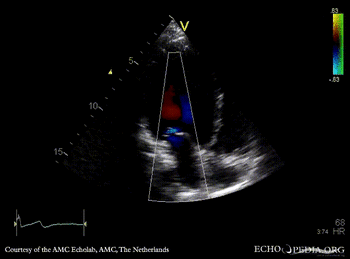

Dilated cardiomyopathy

PLAX: Color Doppler, moderate mitral regurgitation A4CH: dilated poor left ventricle